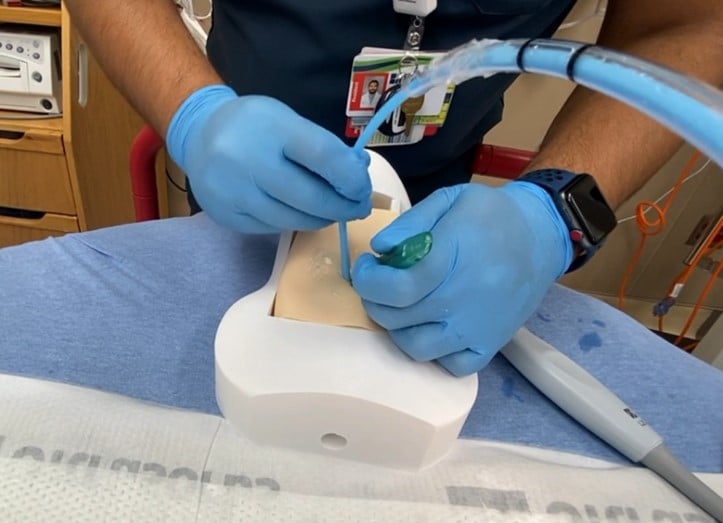

The model can be re-created by downloading the model for 3-D printing, and following the following steps:

- Print the neck model and riser blocks (used to vary the depth of pre-tracheal soft tissue, if desired) on the 3-D printer out of hard plastic polylactic acid (PLA) or similar material.

- Print the larynx on a 3-D printer out of more flexible thermoplastic polyurethane (TPU) or similar material. This allows for a more realistic feel of passing the tube through the larynx, without rigid plastic to for the tube to get caught on.

- Ballistic gel is available commercially with various firmness. Gel that mimics fat tissue works well for this application. Melt the gel in a pot to create slabs of gel of the desired thickness of pre-tracheal soft tissue. This model allows up to approximately 2.5 cm of pre-tracheal soft tissue. Once cool, cut the gel into slabs that fit the model.

- Create an artificial cricothyroid membrane on the model by covering the space for the CTM with a layer of tape.

- For a simulated difficult cricothyrotomy, consider placing the model larynx directly into the neck model without riser blocks behind it. This allows for the largest amount of space in front of the larynx to be filled with ballistic gel acting as pre-tracheal soft tissue.

- Apply generous amounts of ultrasound gel on top of the model larynx, and on top of the ballistic gel to optimize ultrasound images.

- Cut a piece of commercially available artificial skin to size to cover the ballistic gel and complete the model.

In contrast to native cartilage, which is hypoechoic with posterior shadowing, the plastic model of the thyroid cartilage and cricoid cartilage appear hyperechoic with more dense posterior shadowing (below). This model performs well as an ultrasound-guided cric training model. It has realistic anatomy. It models a patient with difficult to palpate anatomy, which are patient who may be difficult to intubate and may be more likely to need cricothyrotomy in the first place. The overlying skin and pre-tracheal ballistic gel can be easily and quickly replaced for the next operator in a training setting. The model allows for performing all the steps of cricothyrotomy including passing the bougie and ETT. The model is durable and re-usable.